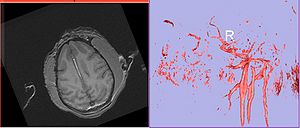

| + | Image:calvin-angio.jpg|'''Calvin axial showing vessel and volume rendering of vasculature''' | ||

- Angio sequence (right name?) has apparently been used for some (7 out of 10) subjects